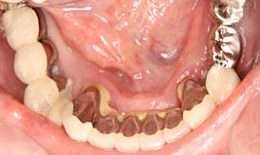

インプラント症例(4) 68歳 女性

治療後

上顎

保存困難な歯を抜歯後、インプラントを7本埋め込み、ボーンアンカードブリッジを装着した